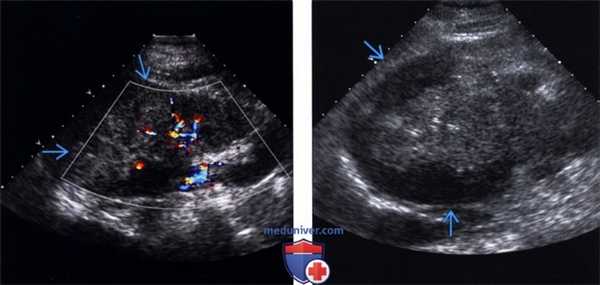

(Левый) На продольном ультразвуковом срезе визуализируется экзофитный гетерогенный светлоклеточный рак почки с задним акустическим усилением от кистозного/некротического содержимого.

(Правый) На УЗ срезе с цветовой допплерографией у этого же пациента с экзофитным гетерогенным раком почки визуализируется выраженный внутренний и периферический цветовой поток.